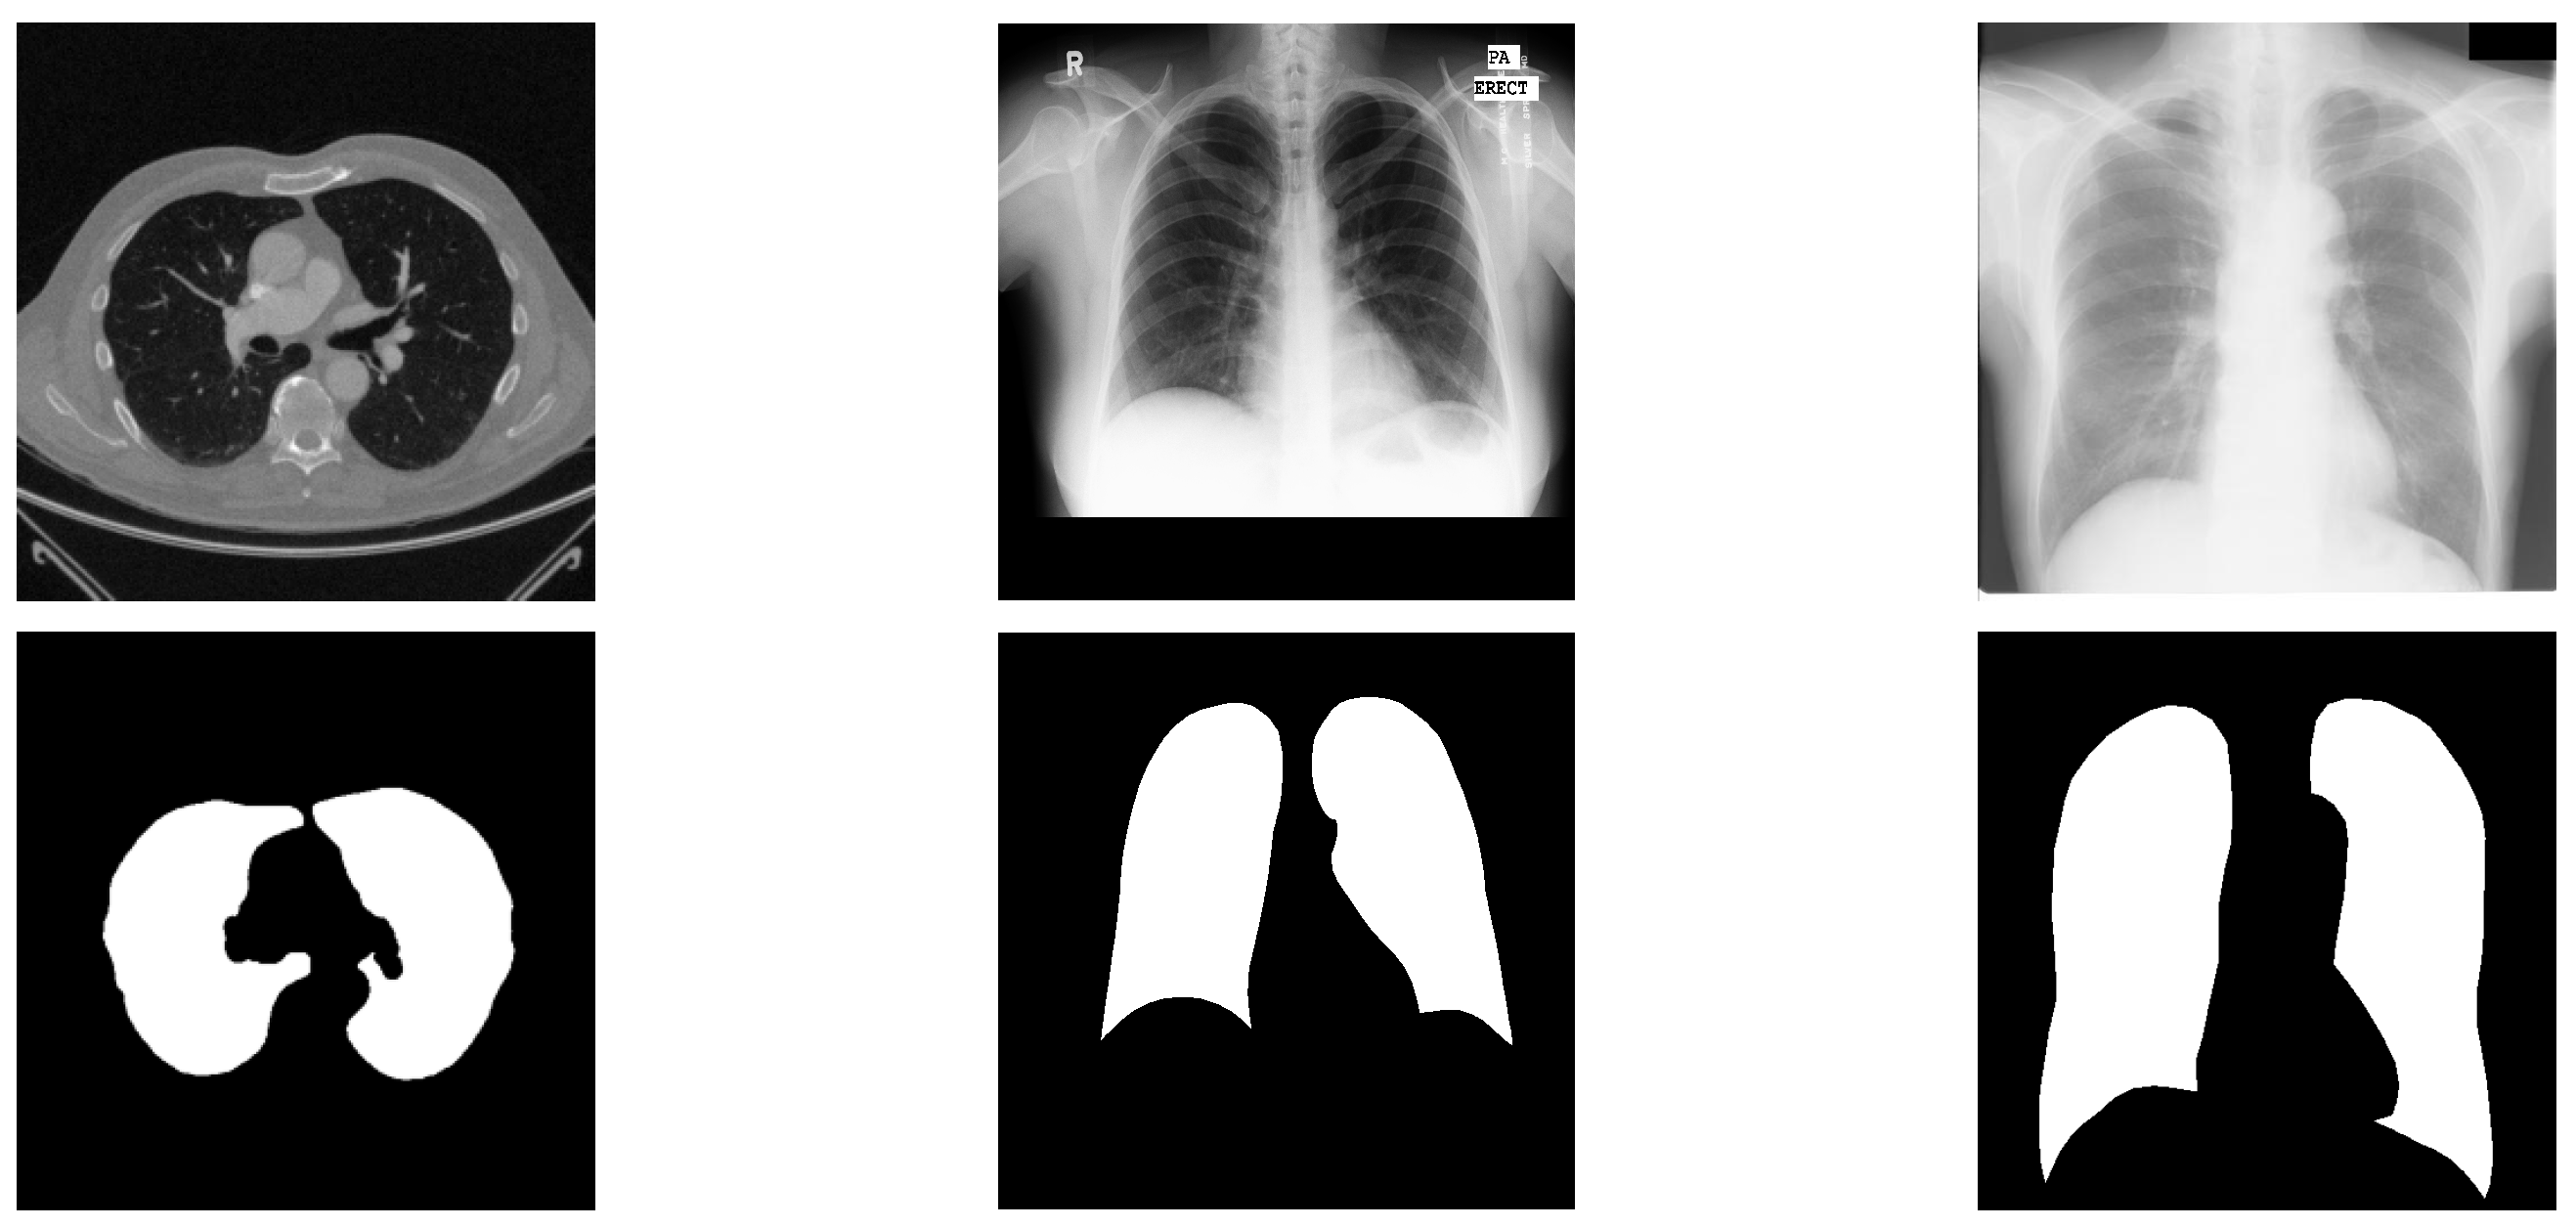

Medical imaging techniques, particularly Magnetic Resonance Imaging (MRI) and Computed Tomography (CT), play a critical role in clinical diagnosis and rehabilitation therapy. Nevertheless, conventional manual diagnostic approaches are increasingly inadequate for the demands of contemporary medical imaging. Consequently, computer-aided diagnostic systems utilizing medical image analysis have drawn significant interest. A pivotal procedure within this domain is the delineation of regions of interest (ROIs) [1]. The COVID-19 outbreak has inflicted substantial damage on global social and economic progress [2]. In this context, CT imaging has emerged as a preferred technique for detecting pulmonary conditions, including COVID-19. Precise segmentation of lung areas from CT scans can support clinicians in disease identification and contribute to controlling viral transmission [3]. Yet, achieving accurate lung segmentation in CT images remains difficult owing to challenges like low texture clarity, insufficient contrast, and variations in anatomical presentation and positioning. Sample CT images from public datasets provided in Figure 1 illustrate the intricate nature of lung segmentation in computer-aided diagnostic systems.

Figure 1.

Representative cases from three datasets, displaying original images alongside segmented lung regions. The figure is arranged into three columns, exhibiting samples from the Luna16, Montgomery County, and JSRT datasets, respectively.